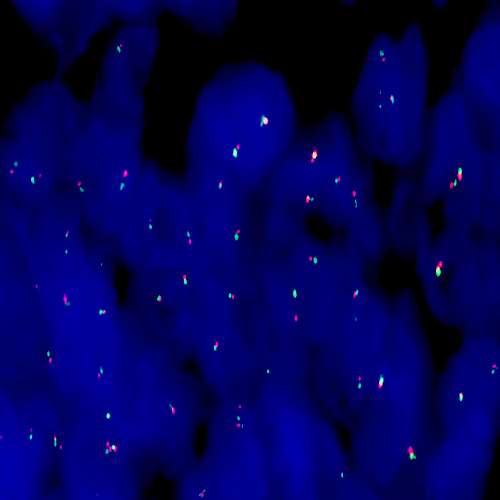

Human placenta: immunohistochemical staining for Vascular Endothelial Growth Factor Receptor-3: clone KLT9

Vascular Endothelial Growth Factor Receptor-3